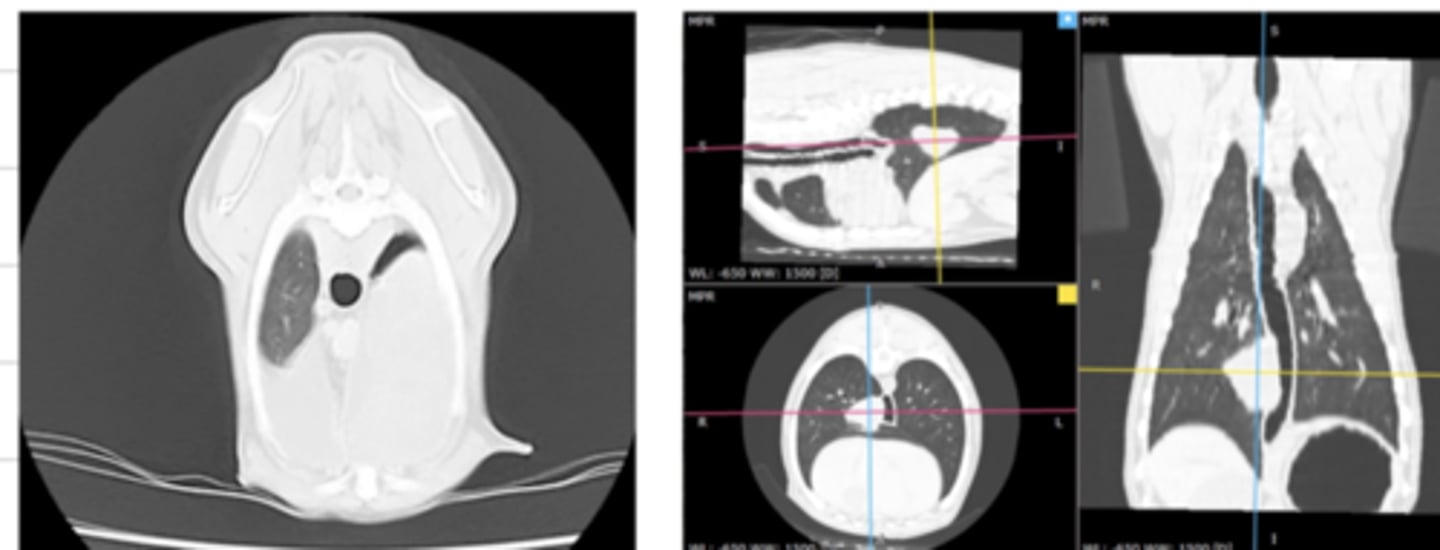

a type of diagnostic imaging where the Xray tube rotates around the patient, generating multiple transverse images of the patient as it rotates.

what is a computed tomography (CT)?

a sequence of 2D images, creating a 3D image- produced in CT

what are "tomographic images"?

bones and lungs

CT is most useful to visualize what structures?

CT

which is more useful to visualize the lungs- radiographs or CT scans?

computed tomography (CT)

what diagnostic imaging technique was used to create these images?

advantages: creates images without overlapping or reconstructions needed

disadvantages: needs sedation/anesthesia, expensive

what are the advantages and disadvantages of using computed tomography (CT) to produce images?

computed tomography (CT)

what diagnostic imaging technique was used to create this image?

computed tomography (CT)

what diagnostic imaging technique was used to create these images?

computed tomography (CT)

what diagnostic imaging technique was used to create this image?